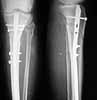

See a recent example in a 76 y.o. female.

![]() |

The picture you showed contradicts your own statement: "Just because i'm not an expert in internal fixation techniques."